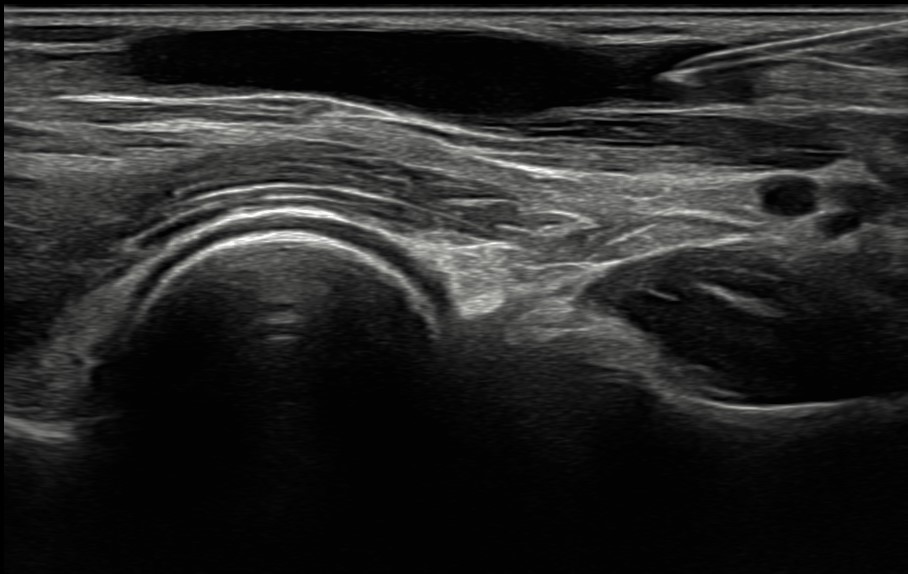

La venopunción ecoguiada se muestra como una técnica segura que ayuda a fomentar medidas de prevención cuaternaria y mejora el control emocional de los pacientes. Actualmente esta técnica se encuentra casi exclusivamente ligada a servicios como urgencias hospitalarias o UCI. Su implementación dentro de la Atención Primaria supone un proceso novedoso y destacable. Hoy en día, las enfermeras especialistas en Familiar y Comunitaria no cuentan en su periodo de residencia con una formación adecuada en esta técnica, por lo que el modelo de formación de formadores y su posterior integración en el EAP se plantea como un proceso innovador y pionero en Atención Primaria del Servicio de Salud del Principado de Asturias. Para iniciar la implementación de esta técnica, se ha realizado formación teórica y práctica conjunta entre residentes de medicina y enfermería.

La venopunción ecoguiada se muestra como una técnica asequible y útil en Atención Primaria, especialmente en casos de venopunción dificultosa.

La disponibilidad de ecógrafos en todos los centros docentes de AP del Principado de Asturias hace posible la implementación de una propuesta innovadora.